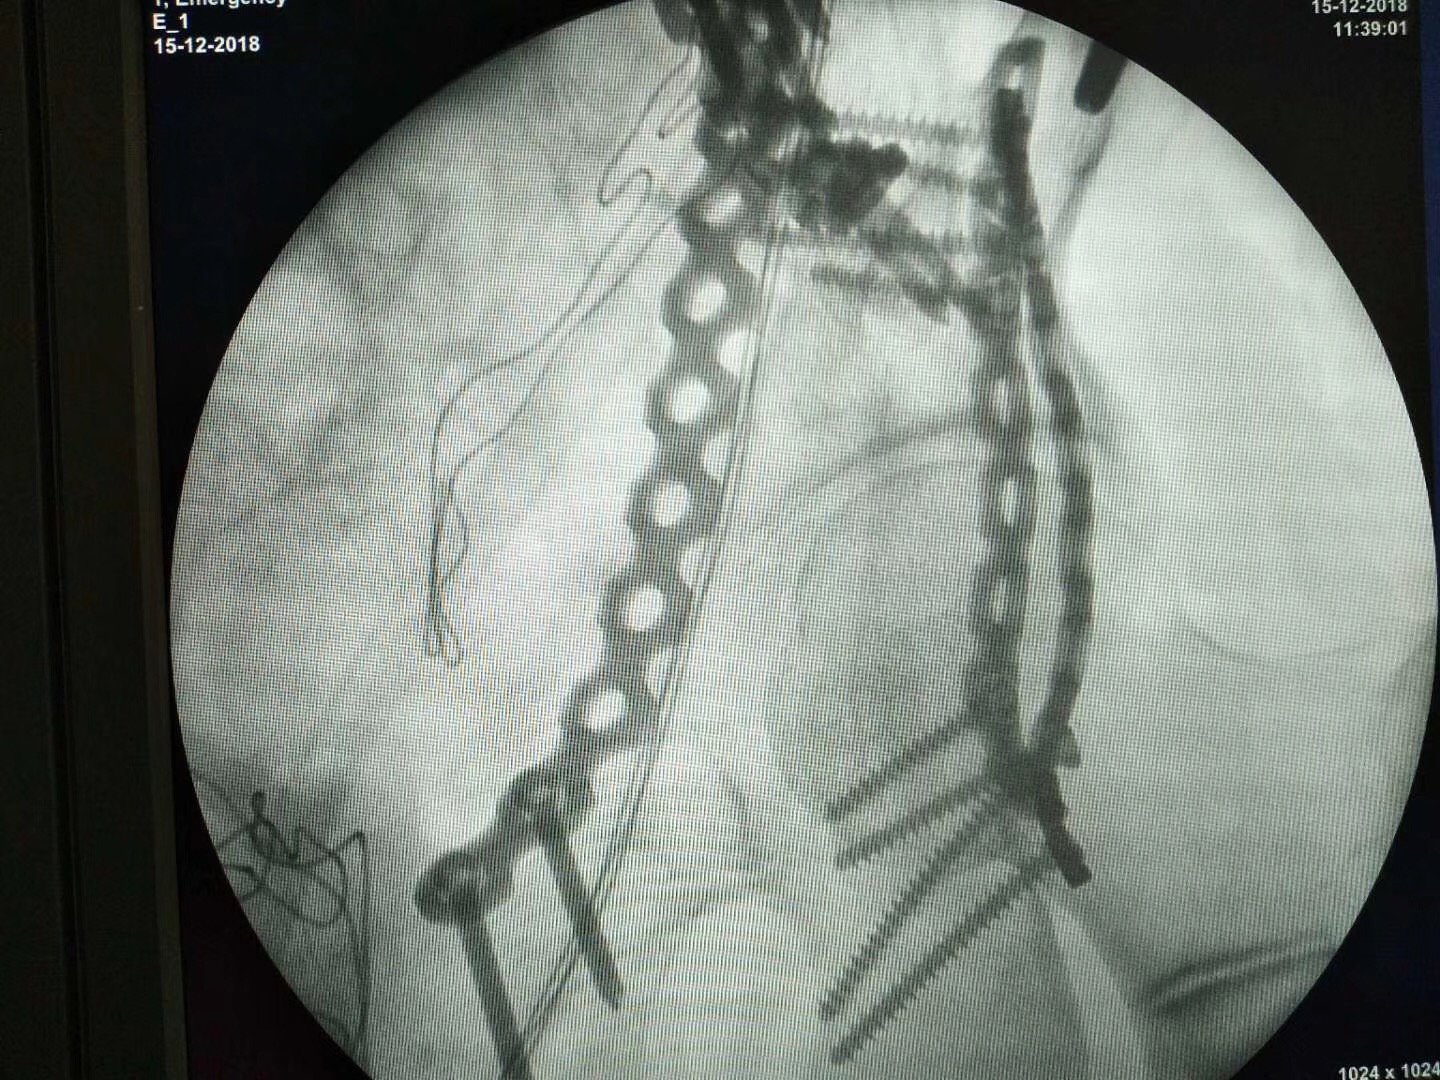

河南省安陽市人民醫院骨三科,接診一位52歲并患者,診斷為骨盆粉碎性骨折。我司收到影像數據后通過3D打印技術制作出3D打印病理模型,配合院方手術方案:切開復位內固定術。

術前影像數據

術中透視